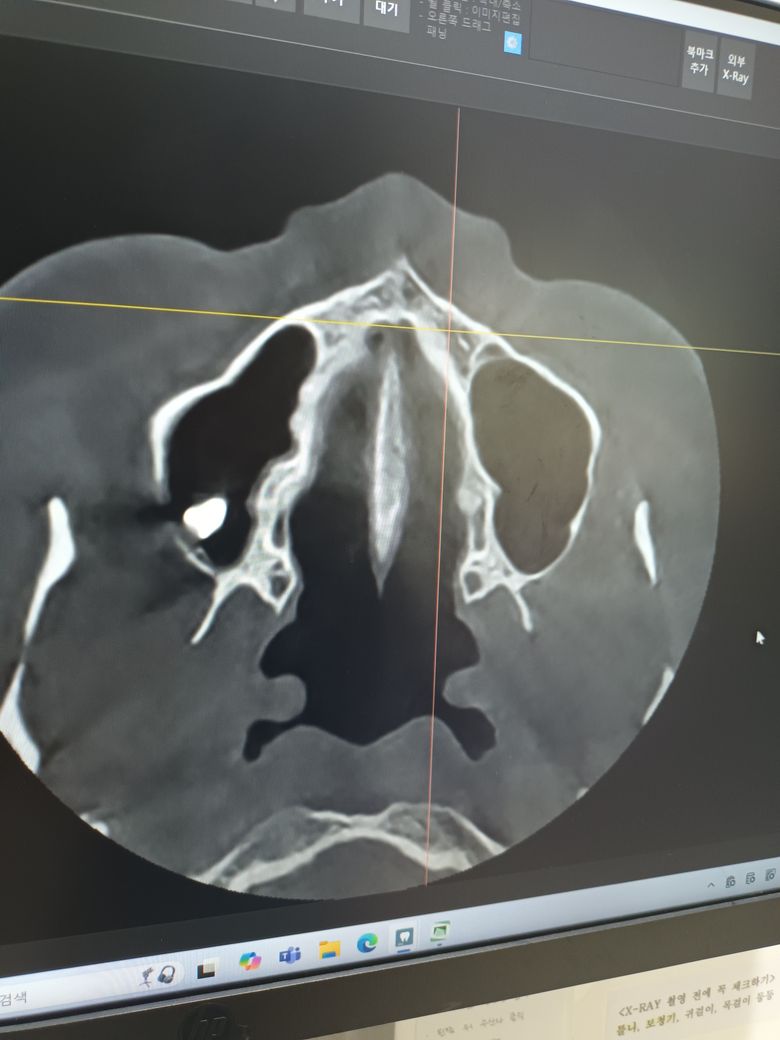

뼈라고 하기에는 다른곳과 비교했을때 임플란트처럼 너무 하얗고 정확히 뭔지 모르겠지만 상악동 안으로 들어가있다면 수술이 필요할것 같다고 하시더리고요.

CT촬영을 했는데 거기서도 뭐가 보이더군요.

칼시펙스누출이 의심이 된다

• 1번 째 사진

• 2번 째 사진